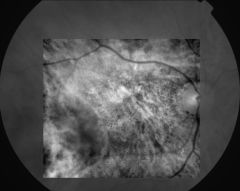

IM000011

IM000012

IM000013

IM000014

IM000015

IM000016